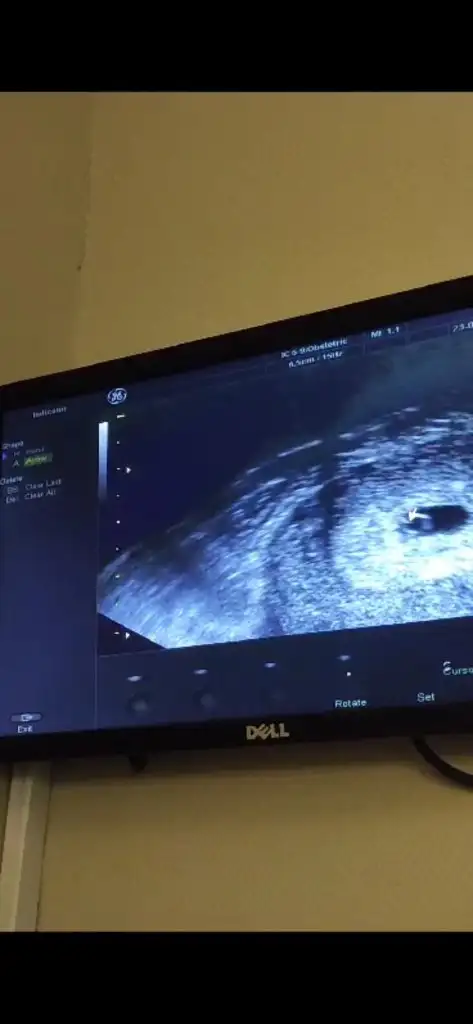

Ayy evet ne güzel var mı senin ultrason fotoğrafınCanım seninle aynıydı değil mi sat 13 Mayısben de bugün gittim bizim de yolk kesesi oluşmuş

Koydum canım yukarıya, bebek daha çok küçük mm söylemedi, 5+3 geç döllenme dediAyy evet ne güzel var mı senin ultrason fotoğrafınkaç haftalık dedi sana bana mm falan söylemedi

Benim kağdın arkasına 6 hafta yazdı ama konulurken 5 falan diyodu hiç anlamadımKoydum canım yukarıya, bebek daha çok küçük mm söylemedi, 5+3 geç döllenme dedi